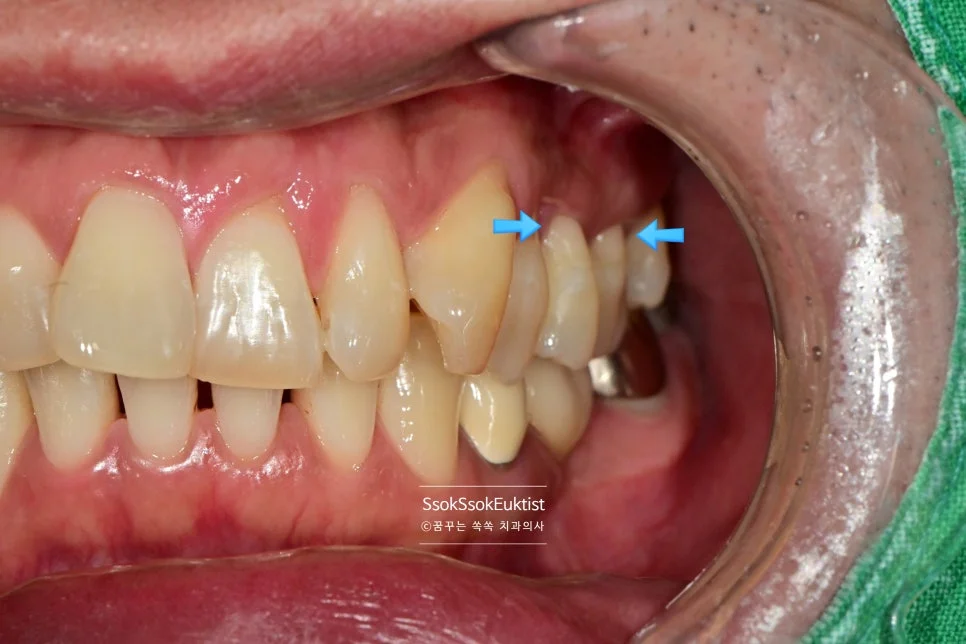

GI를 이용한 치경부 마모증 충전 중

그러고는 GI를 이용해 치경부 마모증을 충전해 주는데요.

어떤가요? GI를 이용한 충전도 꾀나 괜찮나요?

우리 치과에서는 가장 비싸고 심미적인 GI를 사용하고 있습니다^^

한편 그런데 말입니다… 사실 GI의 경우 색상이 거진 정해져 있어 치아가 GI의 색과 유사한 색이면 이렇게 예쁘게 치료가 가능하고, 치아가 보다 밝거나 어두우면 색상이 좀 안 맞아질 수 있습니다^^